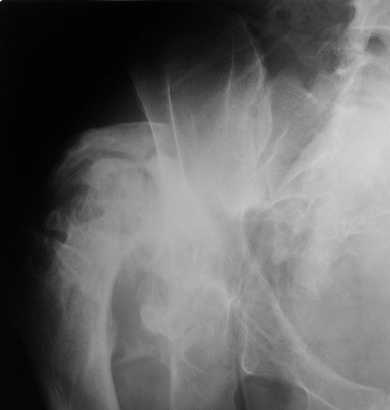

Уважаемые коллеги. Пациент 30 лет 3 года назад в результате травмы получил травматический дефект нижних конечностей до в/3 голеней, был пропущен вывих бедра.

В настоящее время очень неплохо ходит на протезах, движения в неоартрозе близки по объему к здоровой стороне. Основная жалоба - выраженная боль при ходьбе. планируем двухэтапное эндопротезирование - задним доступом мобилизовать проксимальный отдел бедра, резецировать шейку, аппаратом низвести бедро(головку оставить там где она есть, так как больших дефектов не видно(может пригодится в последующем?)). Вторым этапом бесцементное эндопротезирование. Насколько такой вариант реалистичен? Доступ для второго этапа? Может быть другие варианты?С уважением, Максим

Здравствуй, Максим. У пациентов с врождеными вывихами бедра низведение в АВФ получается без отсечения головки и даже без релиза. срок в АВФ примерно 2 недели. Даже если вы планируете первый этап, открыто отсекать головку и оставлять на месте, мне думается неверно. Если так случится, а это весьма вероятно,что головка потребуется для костной пластики, то придется добираться до нее повторно, возникает вопрос"зачем?". На счет доступа, ихмо, предпочтительней задний доступ коль вывих по КТ кзади.

На последнем срезе КТ задний край практически отсутсвует по сравнения со здоровой стороной. Разумеется, что это плоскостное изображение, но головка вывихнулась не только в плоскостную щель захваченную на КТ. Если вы считаете, что удастся установить туда чашку даже низкопрофильную, остается пожелать вам успехов. Но перед этим можно смоделировать установку чашки на скиаграммах КТ.

За пожелание успехов - спасибо, думаю это пригодится, не очень понял про плоскостную щель, специально предоставил срезы на уровне свода - он цел, дефект заднего края ниже, за счет заглубления он будет еще меньше, по данным 3d - должно получиться.

Доступ - по предпочтениям хирурга, я предпочитаю передний с расширенной задней мобилизацией.